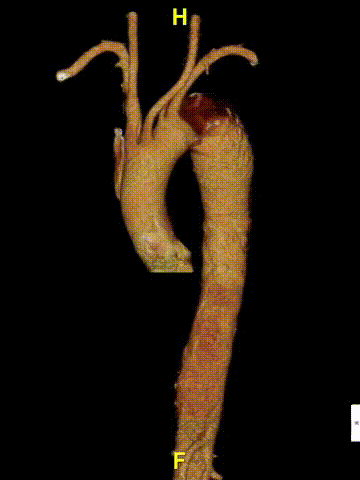

② 八爪鱼支架(多分支支架)的应用

用于内脏区全腔内重建,该技术顺应血流方向,不改变血流动力学,中期疗效确切。

特殊处理:腹腔干可栓塞。

注意:避免倒置操作,减少血栓形成风险。